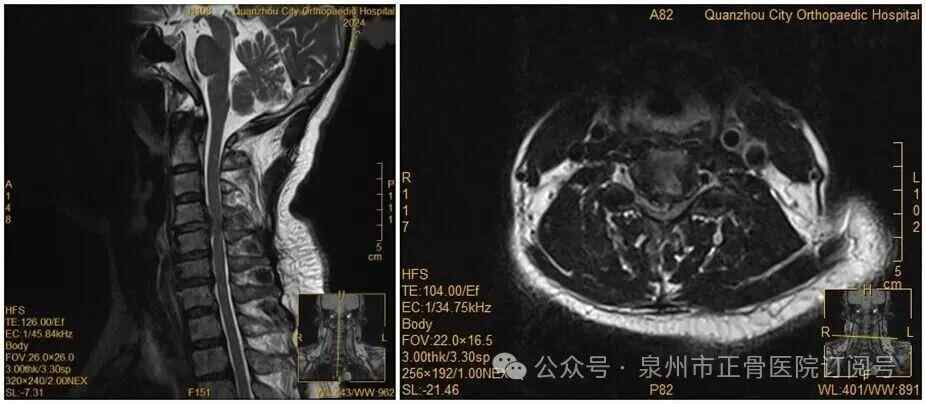

此前,她因手麻、酸痛到医院就诊,被查出颈椎间盘突出症罗瑟汉姆 vs 保顿艾尔宾 。脊柱二科杨声坪主治医师回忆:“会诊时我们明确告知患者,她的颈椎间盘已经巨大脱出,符合手术指征,建议尽快手术。但她坚持想保守治疗。”

没想到,会诊当晚,王女士翻身拿手机的瞬间,双手突然失去知觉——关键肌肌力降至1级或0级,确诊为瘫痪罗瑟汉姆 vs 保顿艾尔宾 。“推测是翻身时,脱出的椎间盘突然进一步卡压到脊髓神经,引发了急性症状。”医生表示。

王女士术前MRI

虽然已经出现了瘫痪,王女士仍然惧怕手术,不愿意接受手术罗瑟汉姆 vs 保顿艾尔宾 。经过医务团队及王女士家人耐心解释及劝解后,王女士才愿意接受手术治疗。医院为王女士紧急实施手术。手术顺利,经过一段时间恢复,她的肢体功能逐渐回归正常。